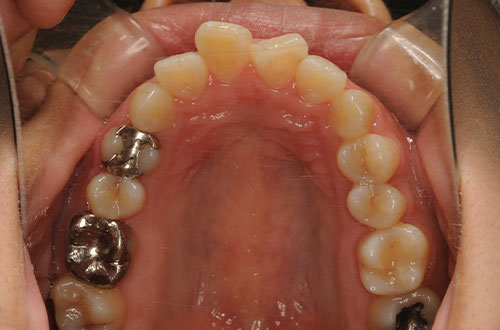

「前歯の部分矯正」~気になる部分だけ治療したい方向け

部分矯正とはその名の通り、「部分的に」歯並びを整える矯正になります。

最後に。部分矯正が「適用にならないケース」もあります

一見、部分矯正で治療できそうであっても、どうしても「他の歯」も動かす必要があり、単純な部分矯正では対応できないことがあります。

これは「噛み合わせ」のためです。